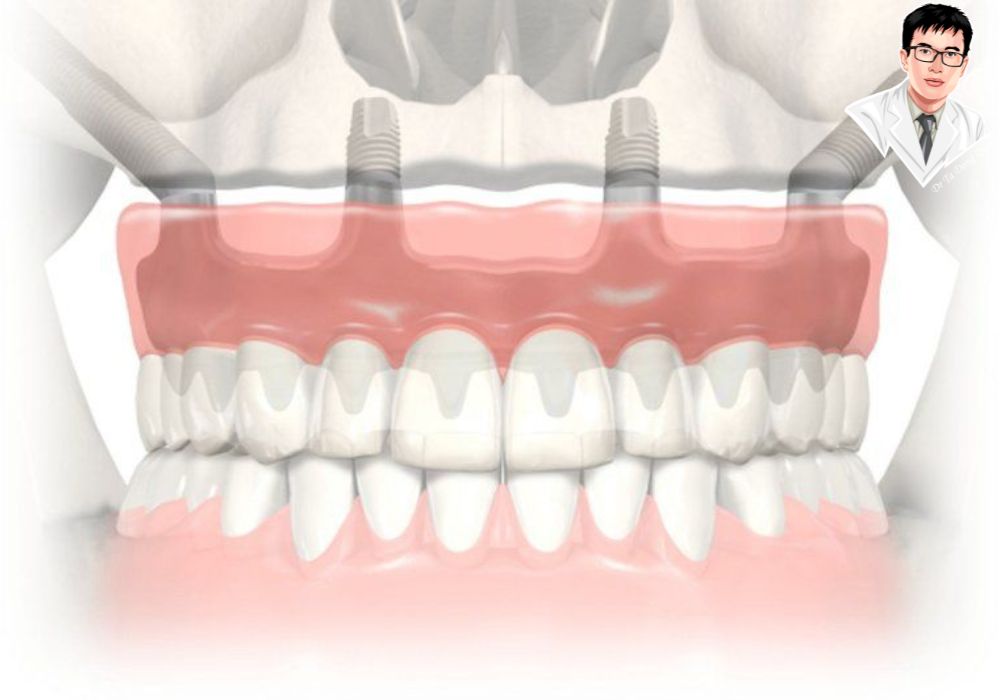

Mô phỏng kỹ thuật cấy ghép implant toàn hàm All-on-4 với cấu trúc trụ implant và hàm giả phục hình cố định.

Với người mất răng lâu năm và tiêu xương nặng, việc trồng răng luôn là một thử thách vì không còn đủ nền xương hàm để đặt trụ. Implant thường hoặc All-on-4 thường thất bại trong những trường hợp này. Tuy nhiên, implant xương gò má được thiết kế đặc biệt để khắc phục điều đó: trụ dài được neo vào xương gò má – nơi có mật độ xương chắc khỏe nhất vùng mặt, giúp cố định chắc chắn mà không cần ghép xương hay nâng xoang.

So với All-on-4: Phạm vi ứng dụng rộng hơn